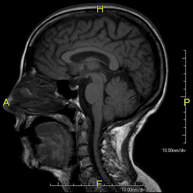

Prueba diagnóstica no invasiva que consiste en la obtención de imágenes de alta definición anatómica del cerebro mediante el empleo de un campo electromagnético y ondas de radio (con un emisor y un receptor). No utiliza radiación ionizante. Indicaciones: problemas vasculares, pérdida de memoria, epilepsia, cefalea, malformaciones, sospecha de tumor, meningitis. - RM Cais